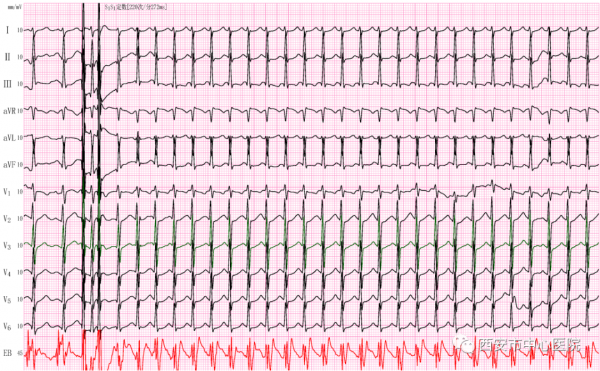

我們透過食管電極發放數個低能量的電刺激(食道調搏),心跳從214次/分的順向型房室折返性心動過速轉換到109次/分的竇性心律(圖3),患者痛苦的表情立刻消失。

(圖3)

張女士,45歲,反覆心悸、胸悶三年餘,再發一週就診。每次發作呈突發突停,持續數分鐘至數小時不等,多次查心電圖均為正常心電圖,臨床診斷:陣發性室上性心動過速待排。

醫生安排了經食管心臟調搏術(俗稱食道調搏)檢查,因每次都不能捕捉到心動過速的圖形,張女士很是擔心會和往常一樣無功而返。順利插入食道電極,我們透過發放提前的電刺激,心電圖由正常的98次/分竇性心律轉變成190次/分的心動過速,張女士連聲說:“對!對!就是這種感覺!謝謝你們,這次終於抓到了!”(圖4)。

(圖4)